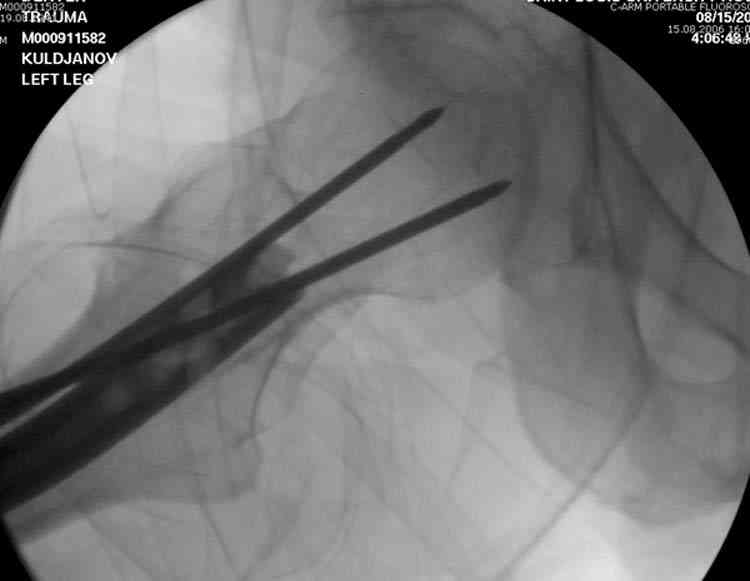

На второй день (7) обнаружен пропущенный перелом,

сделаны Компьютерная Томограмма

и проведены шурурпы через и спереди штифта без удаления.